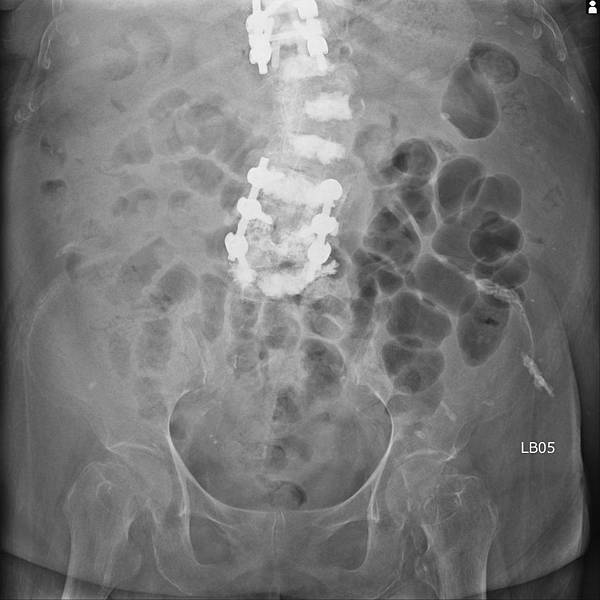

腸躁症有許多種病因,是一種大腸鏡看起來正常的慢性大腸發炎。長期便秘、腹瀉、腹脹、腹痛,不管病人陳述甚麼症狀,KUB絕對不能省掉,之前照過你還是要再照一次。CBC-DC與CRP也不能省,不時會有驚人的發現。